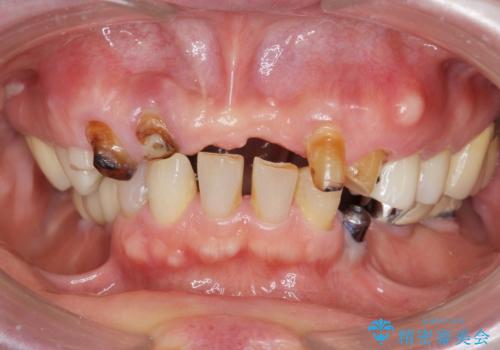

咬合の崩壊 金属床義歯で咬合機能の回復

- 「体調が悪く歯医者に行けない間にどんどん歯が悪くなってしまった、治療をしたい。」と咬合機能の回復を希望され来院されました。

「大規模な手術は避けたい。」と言う希望を鑑み、インプラントではなく残せる歯の連結セラミッククラウンの作製、金属床義歯を用いてしっかりと咬合機能を回復できるよう治療を進めます。